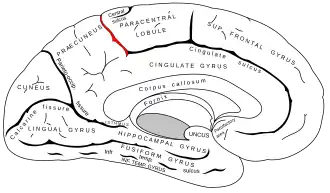

Medial surface of left cerebral hemisphere. (Paracentral lobule is shown in red.) | |